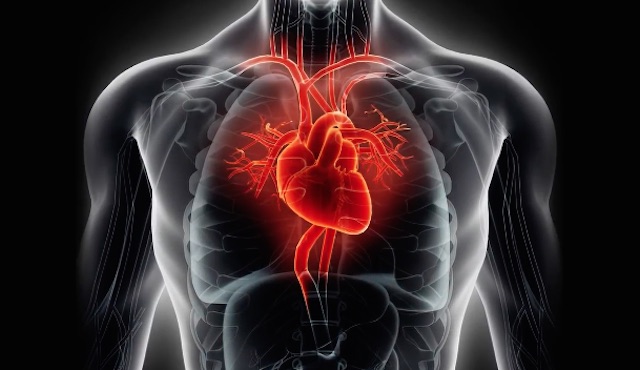

Excellent Cardiovascular Conduct Can Knock 6 Years off Your Organic Age: New Learn about

Excellent cardiovascular well being can knock six years off your organic age, says a crew from Columbia College Scientific Middle in New York Town The researchers examined the American Center Affiliation’s Crucial